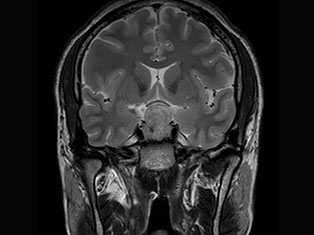

Cerebro Vascular

A stroke occurs when the blood supply to part of your brain is interrupted or reduced, preventing brain tissue from getting oxygen and nutrients. Brain cells begin to die in minutes. A stroke is a medical emergency.